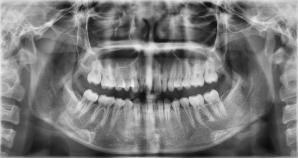

关于网络问诊,相信大家再熟悉不过了,虽然极大的丰富了人们问诊途径,让咨询越来越透明化,但是随之而来的问题也是不可避免的,比如说:同样一种症状,你在网上咨询结果和在实际医院咨询的结果是有差异的,这是为什么呢?拿牙科来举例,通常正规的检查是需要视诊和x光片等为诊断依据的,我们如果没有进行过检查,那么也只能提供一些清晰的口内照片或者面部照片,但这些并不能作为最终方案制定的依据,它只能作为一种参考依据,实际情况仍要以到院医生检查的结果为准!

x光片